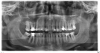

Sanvean Опубликовано 9 января, 2013 Поделиться Опубликовано 9 января, 2013 Здравствуйте! После удаления 16 зуба (на снимке он ещё на месте) отвалился кусок стенки у 36 и пломба стала вываливаться. Что посоветуете делать с 36 и 37? Новые пломбы или коронки?Если коронки, то из какого материала лучше делать вкладки? Ссылка на комментарий

Mane Опубликовано 9 января, 2013 Поделиться Опубликовано 9 января, 2013 Вариант симптоматического лечения- то есть в области 36,37 есть необратимые изменения- карман между зубам. Кость там ушла. И ее там не нарастить. Итак вариант первый- перелечить каналы в этих зубах и сделать в эти зубы вкладки (или другой вариант восстановления культи) и накрыть эти зубы коронками. Но эта процедура временная так как зубы в таком состоянии могут долго не простоять и требуют гигиены очень тщательной (ирригатор). Судя по количеству депульпир зубов гигиена на 3 балла. Вариант второй - радикальный. Удалить зубы 36,37 сразу установить импланты. Потом их спротезмровать и жить спокойно. Вариант надежней предыдущего. При хорошей гигиене простоят всю жизнь. В норм клинике эти усоуги примерно одинаковые по сумме или даже первый вариант дороже. Выбор за вами у кого лечиться. Ссылка на комментарий